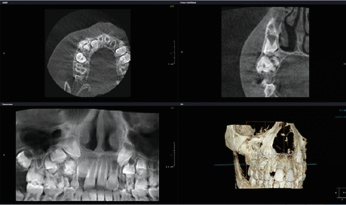

Es ist allgemein bekannt, dass bei der Akquisition einer digitalen Volumentomographie (DVT) mit Artefakten wie Aufhärtungen und Abschwächungen gerechnet werden muss. Obgleich die Rekonstruktionszeit erheblich reduziert wurde, die Auflösung der Aufnahmen immer höher wird und die Bildqualität ständig zunimmt, stellen Artefakte ein stets präsentes Problem in der Verfahrenskette dar. In manchen Fällen machen diese Artefakte gerade für den Ungeübten eine Bildanalyse unmöglich. In der Literatur werden Artefakte wie z. B. Auslöschungs- und Aufhärtungsartefakte beschrieben (Abb.6 u. 7). Sie sind technisch bedingt, während eine andere, sehr wichtige Ursache dieser Artefakte im Patienten selbst zu sehen ist. Da die Belichtung in der Regel mehr als ein paar Sekunden dauert und der Patient im Gegensatz zu der entwicklungsbezogenen These kein statisches Objekt darstellt, kann es passieren, dass er seinen Kopf während der Aufnahme bewegt. In diesem Fall findet man im rekonstruierten Datensatz sogenannte Bewegungsartefakte, die die Bildqualität erheblich beeinflussen können (Abb. 8).

Durch weitere Rechenprozesse können die Daten auf verschiedenste Weise dargestellt werden. Die multiplanaren Rekonstruktionen (MPR) stellen die sinnigste Weiterverarbeitung der Daten dar. Hierbei wird das Volumen durch senkrecht zueinander stehende Ebenen zerlegt, wodurch die Ansichten axial, sagittal und koronal erzeugt werden, ergänzt durch die oberflächengerenderte Ansicht (Abb. 9). Das Angebot entsprechender Bildbearbeitungsprogramme ist vielfältig, zumeist wird das DVT-Gerät mit einer adäquaten Software installiert und eingerichtet – ab diesem Zeitpunkt ist nun der/die Anwender/-in gefordert. In Deutschland ist die Absolvierung eines DVT-Kurses vor Inbetriebnahme eines DVT-Gerätes gesetzlich vorgeschrieben.